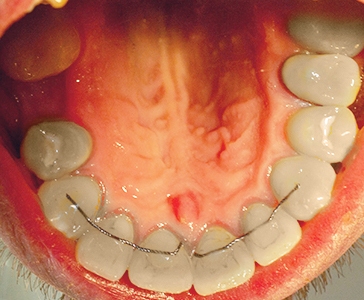

Установлена керамическая вкладка для укрепления зуба (первый этап). Изготовлена и установлена циркониевая коронка на 21 зуб (второй этап)Смотреть работуСрок лечения:2 неделиСумма лечения:35 000 р.